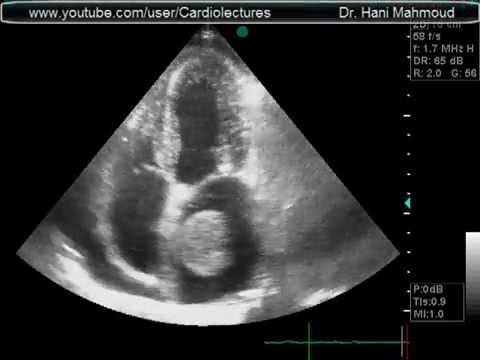

What cardiac condition is demonstrated in this image?

LA thrombus

Metastatic tumor

LV myxoma

Rhabdomyosarcoma

LV Apical thrombus